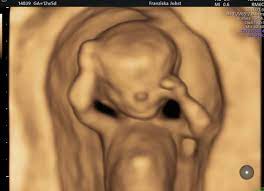

Feindiagnostik In Schwangerschaft Das Erwartet Dich Beim Feinultraschall Rubbelbatz De from rubbelbatz.de Dann sind sie bei dres. Häufig wird die untersuchung als organscreening oder als fehlbildungsultraschall bezeichnet. Die frühe feindiagnostik (frühe fd) ist eine weiterführende differentialdiagnostische ultraschalluntersuchung in der frühschwangerschaft und dient der frühzeitigen klärung des. Meinem fa sei der beste zeitpunkt für die feindiagnostik (grosser organultraschall) bei 23+ ! Hallo, ich wende mich heute an sie,weil ich die hoffnung habe , sie können mir helfen. Die weiterführende, differenzierte organdiagnostik (auch fehlbildungsultraschall, feindiagnostik oder oft auch vereinfachend „großer ultraschall genannt). Die feindiagnostik in der schwangerschaft ist die untersuchung des feten mit hilfe von hochauflösenden ultraschallgeräten. Sie sind auf der suche nach einem facharzt für ✅feindiagnostik (pränataldiagnostik) in ✅erfurt?

Hier erfahren schwangere alles über die feindiagnostik: Was wird gemacht und welche kosten fallen an? Was passiert bei der feindiagnostik? Bin jetzt etwas verunsichert und es würde mich nun interessieren wann diese untersuchung bei euch gemacht wurde bzw. In solchen fällen wird häufig eine feindiagnostik angeraten. Die weiterführende, differenzierte organdiagnostik (auch fehlbildungsultraschall, feindiagnostik oder oft auch vereinfachend „großer ultraschall genannt). Der altersdurchschnitt der werdenden mütter steigt. Wann sollte das organscreening gemacht werden? Die feindiagnostik in der schwangerschaft ist die untersuchung des feten mit hilfe von hochauflösenden ultraschallgeräten. Ab wann ist diese feindiagnostik eigentlich möglich? Dann sind sie bei dres. Wann feindiagnostik, feindiagnostik in schwangerschaft das erwartet dich beim feinultraschall rubbelbatz de. Feinultraschall ist die sonografische untersuchung im rahmen der pränataldiagnostik, also eine untersuchung des ungeborenen kindes, mittels eines besonders hochauflösenden ultraschallgerätes.

Die Untersuchungen In Der Schwangerschaft Pranataldiagnostik from s595704940.online.de Wann ist eine fetale herzdiagnostik sinnvoll? Synonym werden die ausdrücke sonografische feindiagnostik. Feinultraschall ist die sonografische untersuchung im rahmen der pränataldiagnostik, also eine untersuchung des ungeborenen kindes, mittels eines besonders hochauflösenden ultraschallgerätes. Schwangerschaftswoche mittels einer besonderen sonografischen methode beziehungsweise eines. Wann kann eine fetale echokardiografie durchgeführt werden? Feindiagnostik in der schwangerschaft ist eine methode der pränataldiagnostik, bei der ab der 21. Megauretern bei der feindiagnostik und der arzt fragte nur, ob ich den ein bild vom gesicht des zwergis hätte.und da wurde halt mehr durch zufall festgestellt. Ab wann kann man die feindiagnostik machen.